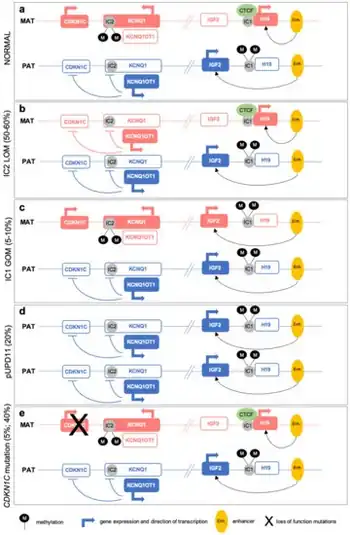

Most (>85%) cases of BWS are sporadic, meaning that, typically, no one else in that family has BWS, and parents of an affected child are not at increased risk of having other children with BWS. However, some (<15%) cases of BWS are familial, meaning that a close relative may also have BWS, and parents of an affected child may be at increased risk of having other children with BWS. BWS has been shown to specifically involve mutations in a defined region on the short arm of chromosome 11 referred to as 11p15.5, that leads to overactivity of the IGF-2 gene (growth factor) and/or no active copy of CDKN1C (inhibitor of cell proliferation gene).

BWS can be caused by a range of different genetic defects. Over five distinct errors involving 11p15.5 have been identified in different BWS patients. Some patients have maternal chromosomal rearrangements of 11p15.5. Other patients have paternal uniparental disomy (UPD) of chromosome 11, meaning that the maternal copy of this chromosome is replaced with an extra paternal copy. Many other patients have abnormal DNA methylation in different areas of 11p15.5, meaning that normal epigenetic marks that regulate imprinted genes in this region are altered. A few other patients have a single gene copy located within 11p15, instead of two copies.

Genes involved are IGF-2, CDKN1C, H19, and KCNQ1OT1.[19]

Association with CDKN1C

CDKN1C is a protein coding gene that encodes a cyclin-dependent kinase inhibitor that acts as a negative regulator of cell proliferation, effectively making CDKN1C a tumor suppressor gene. CDKN1C also works during fetal development, preventing the fetus from becoming too large. It is located on the short arm of the human chromosome 11 in the ICR2 region, along with many other imprinted genes. Since CDKN1C is preferentially maternally expressed, hypomethylation in the ICR2 region of the maternal allele can result in pathologies such as cancer or a defect known as Beckwith-Weidemann Syndrome. Beckwith-Weidemann Syndrome (BWS) may also be brought about by CDKN1C 11p15 epimutations. It may also be a result of deletions of small amounts of DNA that cause chromosomal abnormalities, rendering the gene inactive. This leaves only the paternally expressed IGF2 to promote cell proliferation. The reduction of growth restriction results in the overgrowth of many tissues, leading to the common symptoms of BWS. These symptoms may include macroglossia, organomegaly, periorbital fullness, and hernias. Knockout models for CDKN1C in mice do exist; in fact, many of the affected offspring exhibit fetal and neonatal lethality and have most of the features related to Beckwith-Weidemann Syndrome.[20]